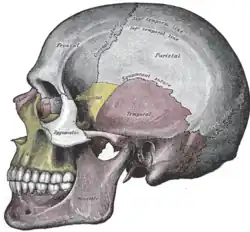

Vista lateral do crânio.

Vista lateral do crânio. -